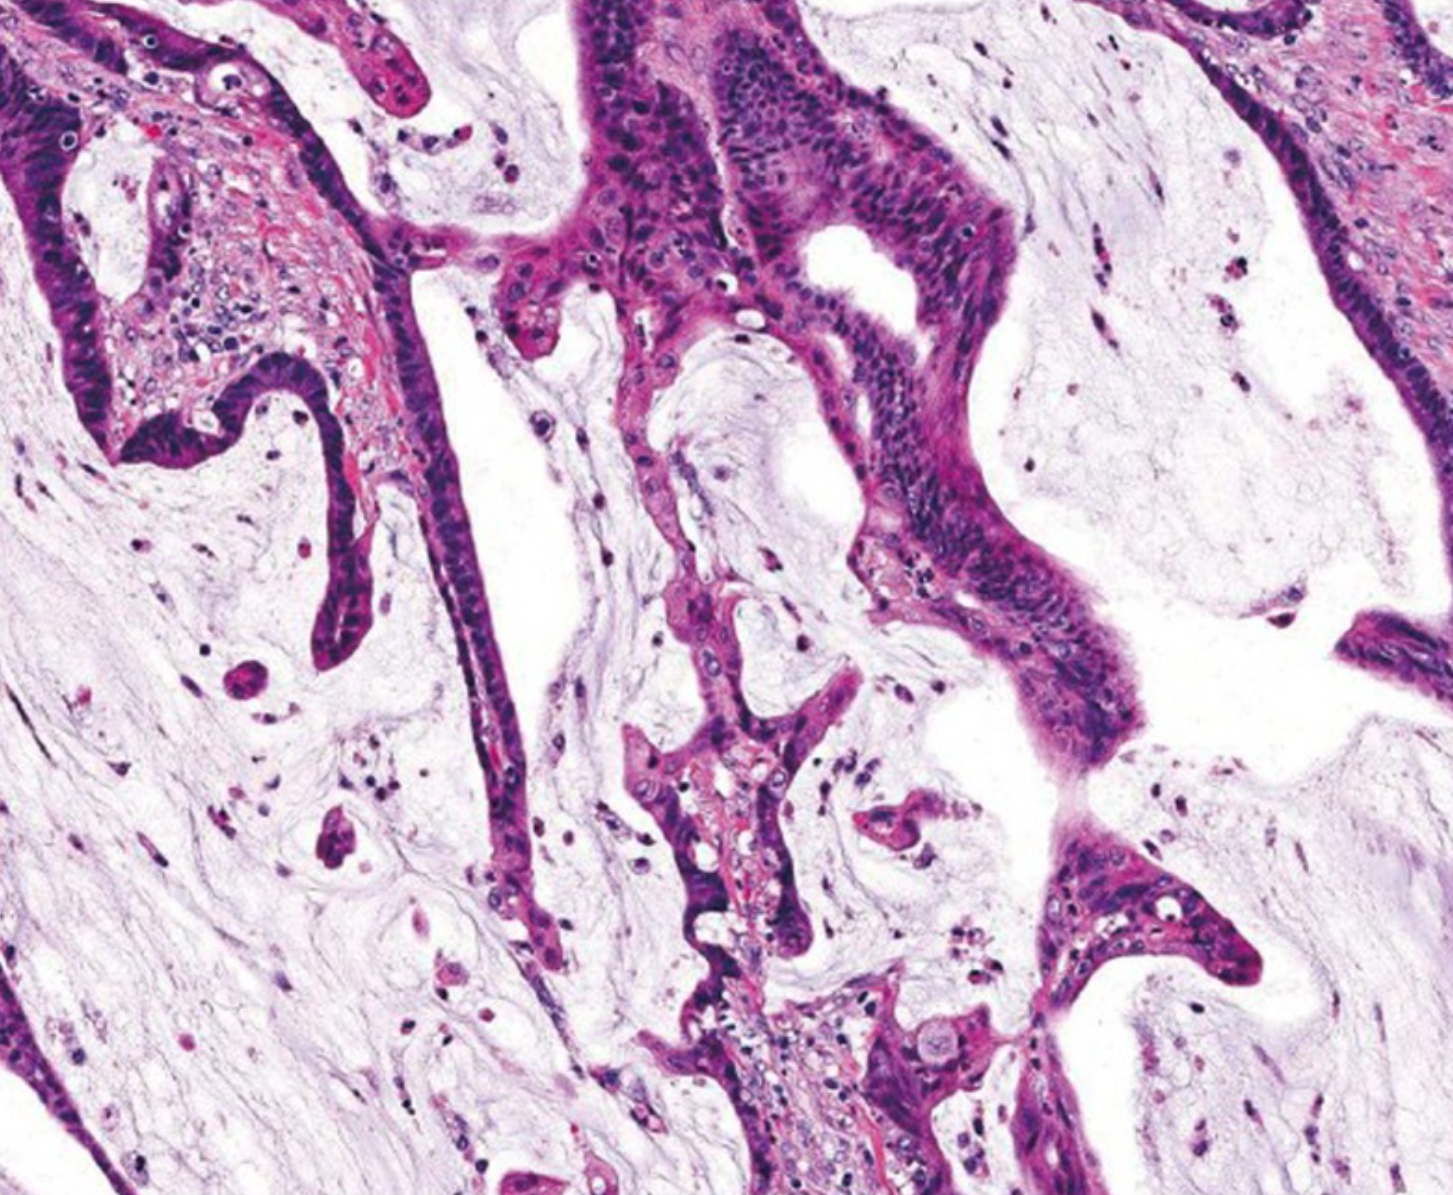

这种特殊类型的结直肠癌的定义是肿瘤体积的50%由细胞外粘蛋白组成。 具有明显黏液成分(10% ~ 50%)的肿瘤通常被称为具有黏液特征或黏液腺癌。 黏液腺癌典型表现为大的腺状结构和细胞外黏液池(图3)。 可以看到数目不定的单个肿瘤细胞,包括印戒细胞(signet ring cells)。 在不同的研究中,粘液腺癌与常规腺癌的预后存在争议。 相比之下,微卫星稳定(MSS)的黏液腺癌表现出更强的侵袭性,特别是在晚期发现时。

若本图无法展示,请更换浏览器查看

图3.粘液腺癌显示丰富的细胞外黏液(原图×200) [4]。